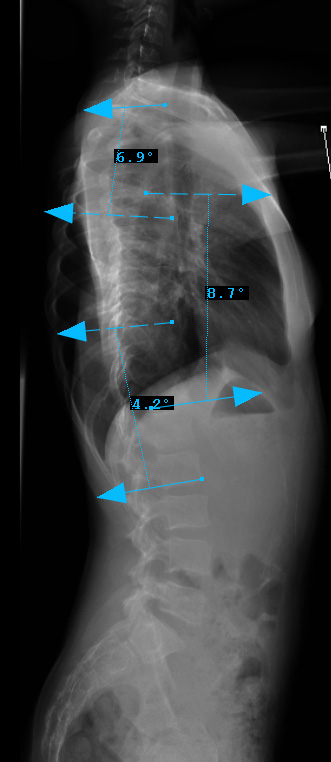

Preop LAT View

Sagittal Modifier ( - )

T5-T12 in the <10o range

Therefore, Classification is Type 3B-